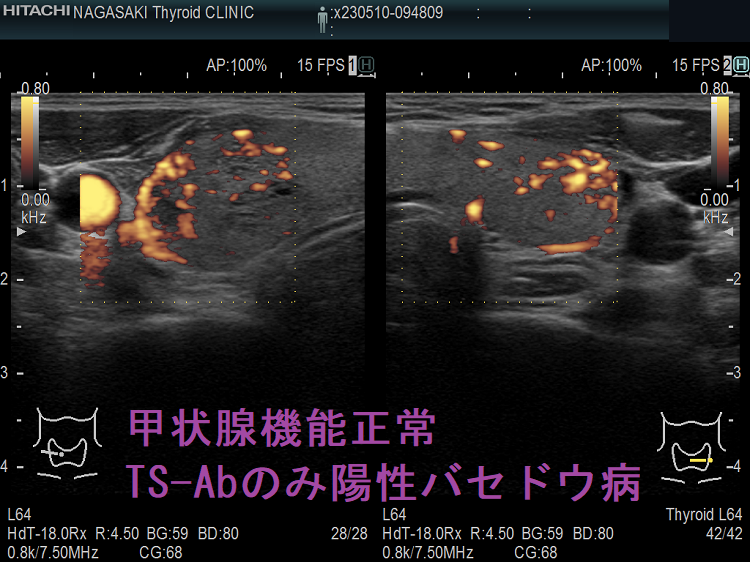

甲状腺機能正常、TSAbのみ陽性バセドウ病 超音波(エコー)画像 下甲状腺動脈血流速度(ITA-PSV)は正常

TSAb 3000%台 甲状腺機能正常バセドウ病;この状態が3年以上続いており、TSBAb(TSHレセプター抗体[阻害型]、甲状腺刺激阻害抗体)が拮抗している可能性を考えます。